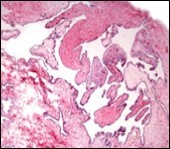

Figure 2.Ciliated cutaneous cyst with an undulating layer of ciliated cuboidal epithelium and supporting fibrous tissue framework (12).

Typically, cutaneous ciliated cyst is a simple cyst which demonstrates a layering of pseudostratified ciliated columnar epithelium recapitulating conventional epithelial lining of the fallopian tube. As the cutaneous ciliated cyst demonstrates a morphological similarity to the fallopian tube lining epithelium, a Mullerian origin is indicated. Gross examination of cutaneous ciliated cyst depicts a solitary, mobile, non-tender, fluctuant, firm or soft to cystic lump with a fibrous wall and abundant amount of circumscribing adipose tissue. Cutaneous ciliated cysts are of a variable dimension. Cut surface usually displays a unilocular cyst impacted with clear, serous fluid, an attenuated smooth, greyish/ white cyst wall incorporated with incomplete septa traversing the cyst 6, 7.

Cutaneous ciliated cyst is layered with a singular layer of ciliated epithelial cells which are chiefly constituted by cuboidal to columnar epithelium, traversed by partially configured fibrous tissue septa with an admixture of randomly dispersed, intraluminal papillary projections akin to those cogitated in the fallopian tube. Superimposed epithelium is inundated with well vascularized, parallel bundles of collagen although smooth muscle is absent 7, 8.

Cystic structures cogitated within deep dermal or subcutaneous tissue can be impacted with haemorrhagic fluid. Cyst lining is smooth, regular and is essentially composed of a singular layer of columnar epithelium with focally pseudostratified columnar epithelium, a circumscription of loosely configured, well vascularized, fibroconnective or fibrocollagenous tissue and an absence of inflammatory infiltrate.